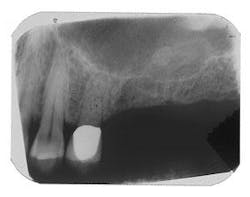

Figure 1 - Panoramic of hopeless teeth under fixed bridge

Figure 2 - CT scan showing large bone defect